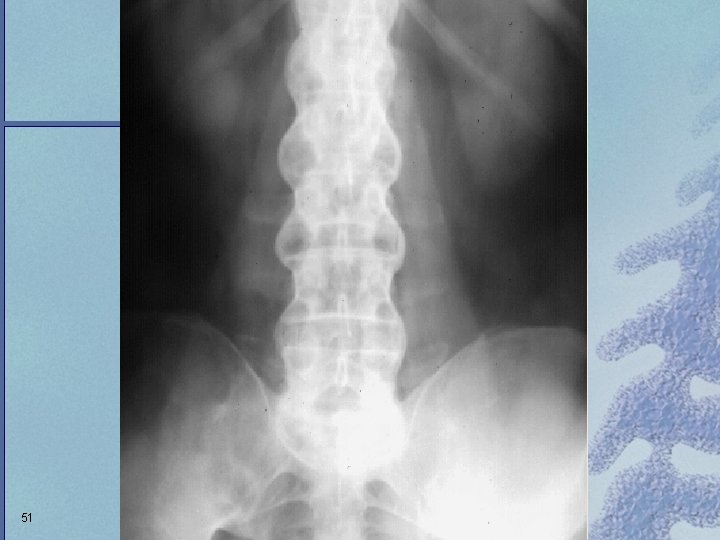

Fusion of Bilateral Sacroiliiac Joints 50

51